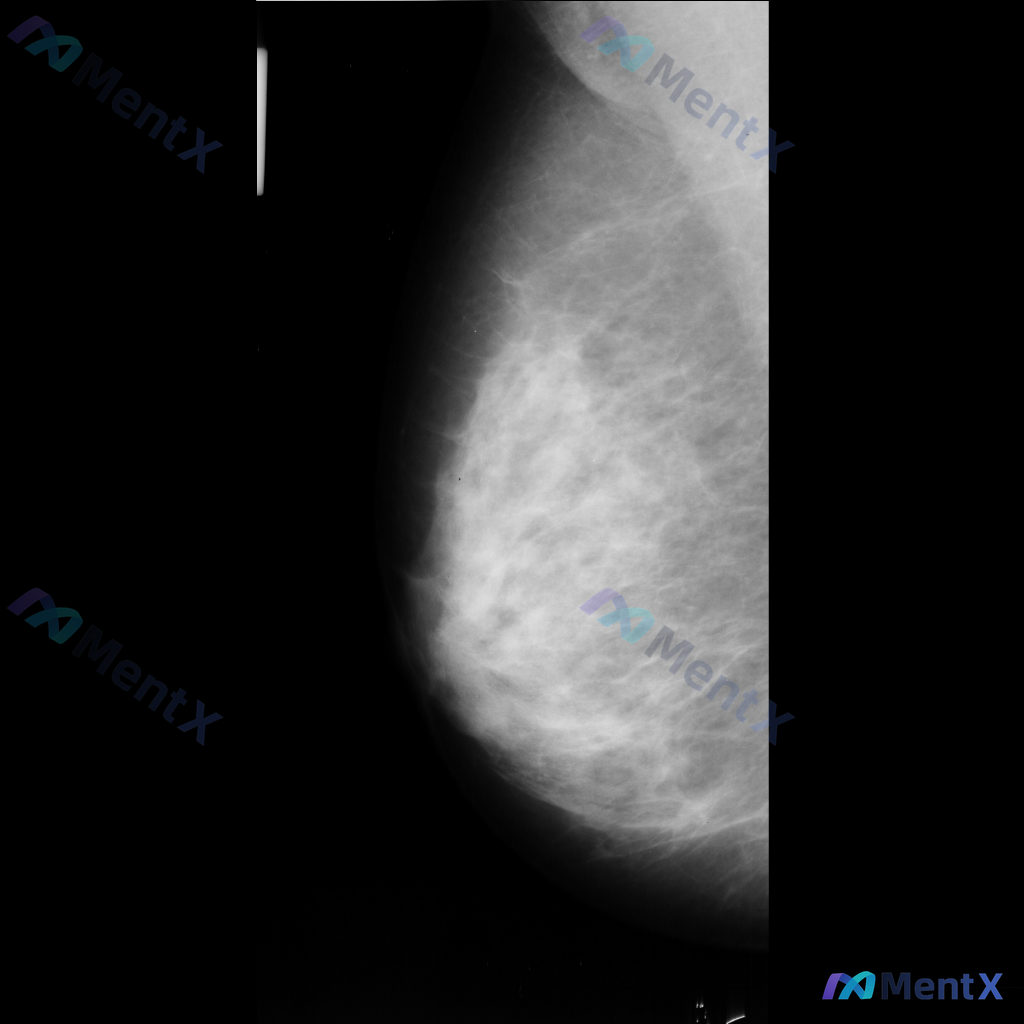

整理到一份乳腺钼靶影像的病例资料,目前只有单侧MLO位片: 影像表现:在乳腺中央偏上方区域可见一个高密度、类圆形的单个钙化影,边界清晰,大小约2-3毫米。目前没有看到明确的肿块、结构扭曲或不对称致密影等其他可疑征象。 想请教大家,单看这组单侧MLO位的影像表现,你会先怎么判断这个钙化的性质倾向?后续...